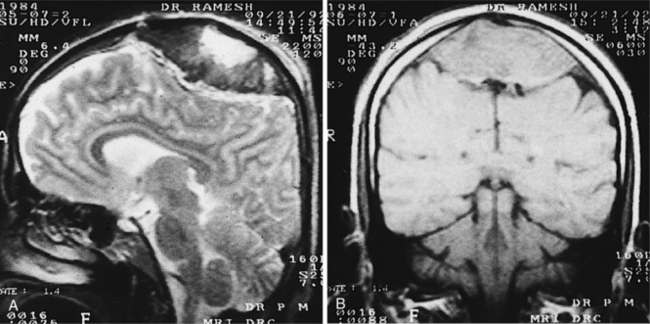

Magnetic resonance imaging (MRI) allows for the identification of an ischemic event within 2 to 6 hours of onset. The soft tissue contrast and multiplanar imaging capability offered by MRI have led to its wide acceptance as the method of choice for high-resolution brain imaging. Diffusion-weighted MRI (DWI) provides an indication of the brain tissue’s physiologic response to ischemia and can document the evolution of stroke. Because halting the evolution of the stroke is the therapeutic goal, DWI may be useful in the evaluation of therapeutic effectiveness. Perfusion imaging uses a tight bolus of paramagnetic contrast agent and a sequence of rapid MRI scans to detect the passage of the agent through the brain tissue.21 MRI stroke sequences can be used as a measure of ischemic penumbra and can help pinpoint potentially salvageable brain tissue, helping to identify who is going to be a good candidate for the later window of intervention using thrombolysis and who is not.86